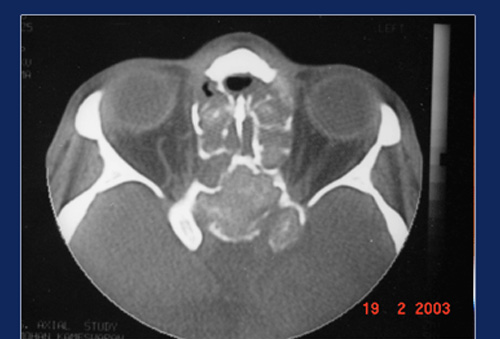

Chronic indolent or granulamatous fungal disease affects apparently healthy individuals. Usually the disease affects the orbit and brain. Though the starting point may be in the sinus, once the fungus gains entry into the orbital fat or brain it spreads like wild fire. The body’s own defence mechanism puts up a fight and granulomas form. It is usually very thick scar tissue. Cutting instruments have to be used even to take a biopsy.

Destruction of tissue planes are typical and it makes en masse excision difficult

Small lesions respond well to anti fungal treatment. But large lesions involving the orbit and cranium are refractory to antifungal treatment. Surgical excision combined with longterm antifungal treatment helps in controlling the disease. Aspergillus is the commonest organism and hence it also called chronic indolent aspergillosis.